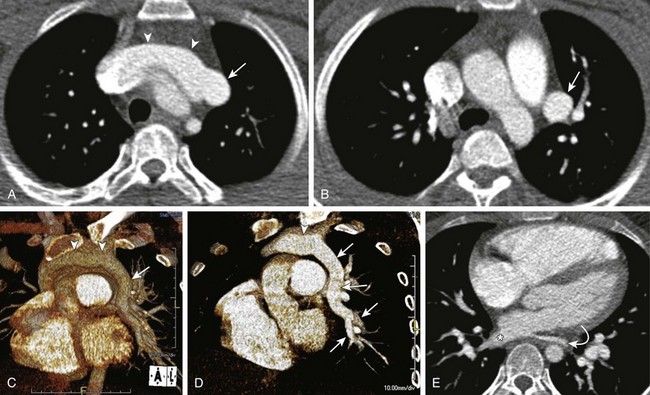

Figure 53-26 An 8-year-old with a family history of hereditary hemorrhagic telangiectasia and a positive echocardiogram for a pulmonary arteriovenous malformation (AVM).

A, An enhanced sagittal reformatted computed tomography (CT) image shows a large AVM (arrows) in the superior segment of the right lower lobe. Coronal-oblique volume-rendered (B) and coronal maximum intensity projection (C) CT angiography images show a large AVM (straight arrows) with a feeding artery from the right main pulmonary artery (RPA) and a large draining vein into an enlarged right inferior pulmonary vein (curved arrow). Pulmonary angiogram images (D and E) demonstrate a large AVM that correlates well with the CT angiography findings. A postembolization image (F) with platinum coils shows partial obliteration of a large portion of the lesion.

Pulmonary AVMs may be simple or complex. Approximately 80% to 90% of the simple angioarchitecture of pulmonary AVMs, consisting of single or multiple feeding arteries, all originate from one segmental artery and are connected directly to a single draining vein.11 Typically, both the artery and vein are dilated and are connected by the aneurysmal sac. The remaining 10% to 20% of cases involve complex architecture lesions, with two or more feeding arteries arising from at least two different segmental arteries and connecting with at least two draining veins.11 Nearly 5% of patients with HHT have multiple pulmonary AVMs.75